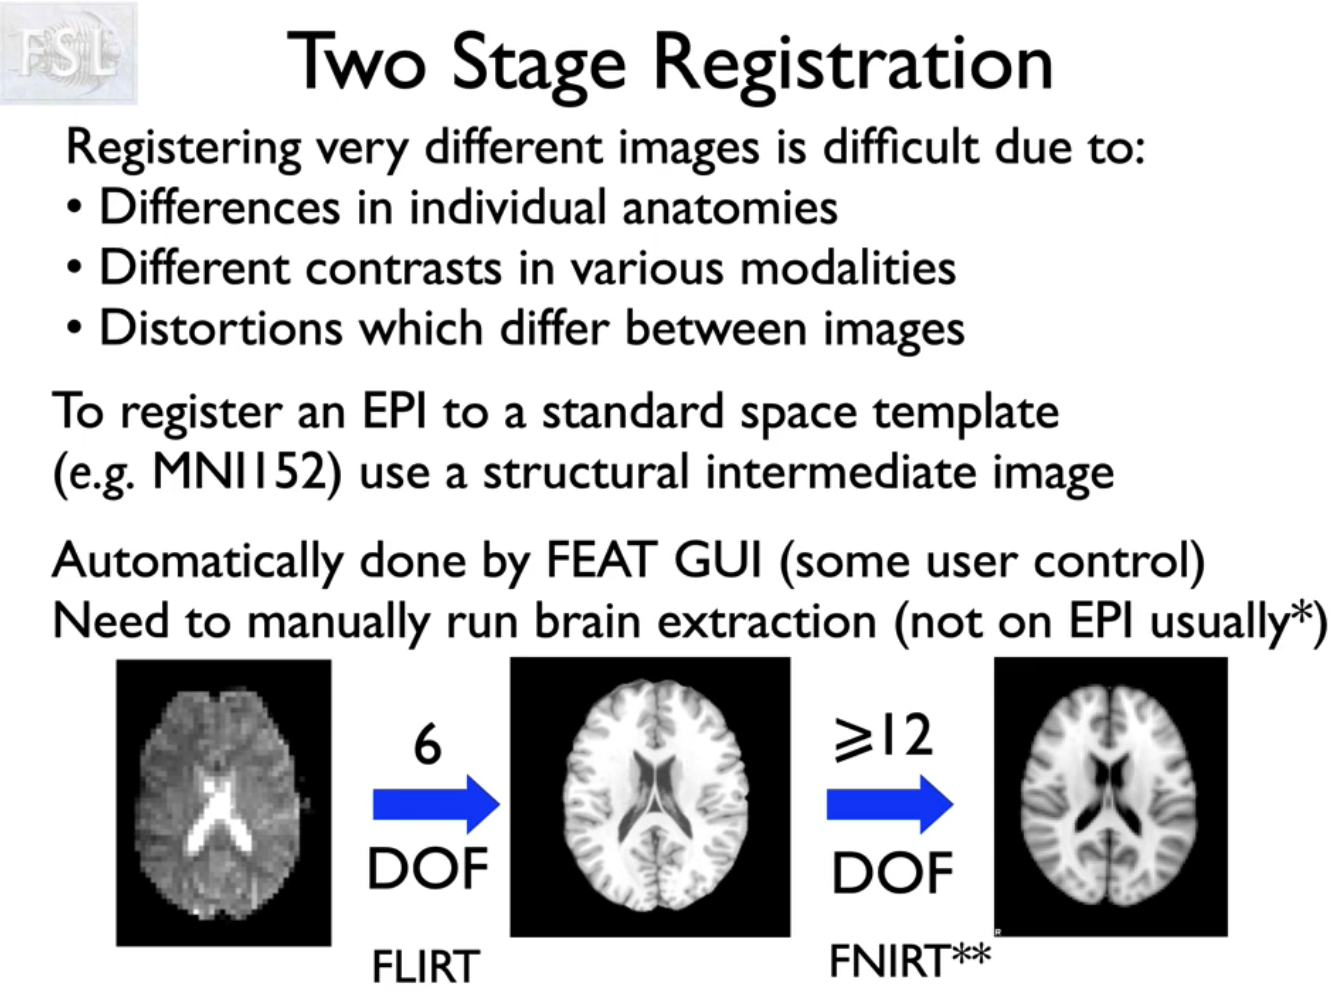

功能成像或扩散成像,然后我们也有一个特定的t1加权结构扫描主题,我们还需要将东西放入标准空间,因此我们现在有三个不同的空间,我们将进行多阶段配准,既可以在我们想要的任何空间组合之间移动,也可以让我们更好地配准

如图,我们先把epi功能像配到同一个病人的T1w上,只需要用自由度为6,线性配准进行,再把T1W配到标准空间。这时由于是不同个体,解剖差异较大,使用自由度12,非线性配准(FNIRT)

为什么这么做?参考视频里的解释。(gzh)